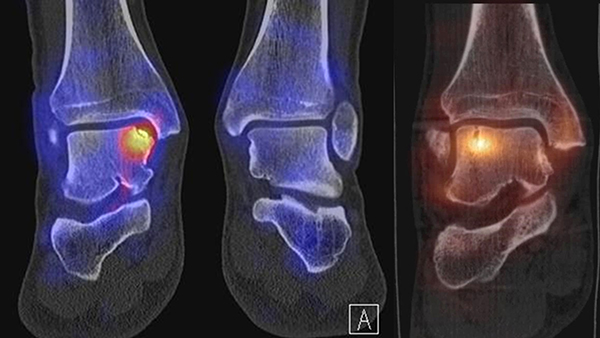

Die Abbildungen 4.2.a bis d zeigen den typischen Aspekt einer talacalcanearen Coalitio. Es besteht nur eine linksseitige, symptomatische Coalitio talocalcaneare (4.2.a und c); das 35 Tage zuvor angefertigte MRT zeigt keine auffälligen Signalveränderungen (4.2.b und d).

Abbildung 4.3. zeigt die Ursache für rechtsseitige Sprunggelenksbeschwerden bei einem Patienten mit talocalcanearen Coalitionen: nur die osteochondrale Läsion an der distalen rechten Tibia ist die Ursache des Schmerzes. Die bilateralen talocalcanearen Coalitionen sind asymptomatisch.